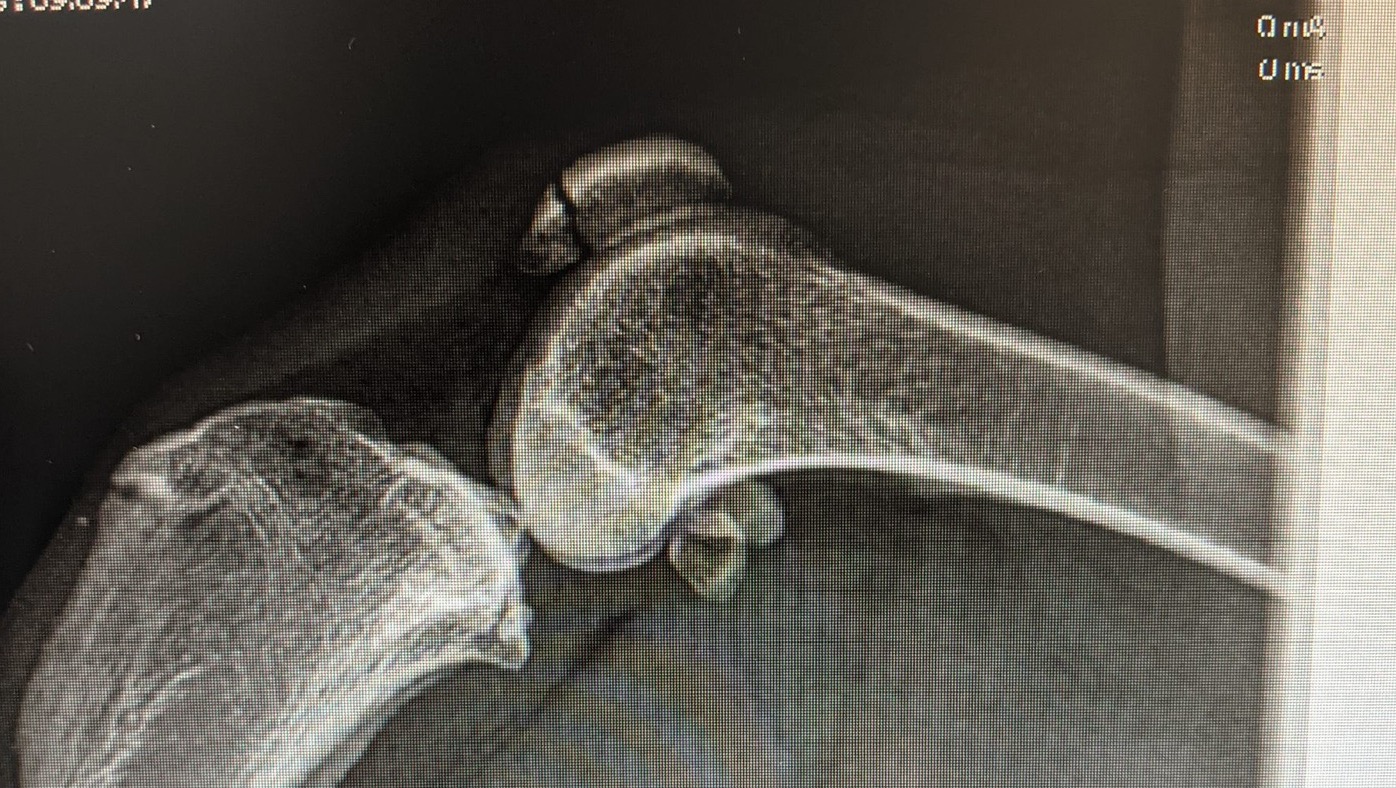

My name is Ginny (like a gin&tonic) and I’m a 1 year old SWEETHEART with a broken patella! I love swimming in the summer but my day of fun ended in the worst way by me bumping my kneecap pretty hard onto the dock when jumping up from the shore. My X-rays show a clean break right through my rear left patella which my vet along with 2 board certified orthopedic surgeon vets have agreed needs immediate surgery to fix. We’ve been told that the muscles in that area are super strong and are pulling the split bone in opposite directions and will not heal together without surgery stabilization. My pet insurance was 2 days away from going into effect and my mom is completely unable to afford my treatment as SHE is undergoing treatment herself for an injury that has had her medically prescribed to be off work since December 2020. My initial vet visit with xrays and pain meds cost $470 that was paid for with Care credit, as my vet does not do payment plans. **The surgery is scheduled for Thursday 7/8 and gave an estimate for between $3,757 - $4,257. The goal has been updated to include both the initial vet visit costs as well as the high end of the estimate for surgery incase it comes to that. After the surgery is finished and we are given the official amount due, we will update the goal to reflect. I am an emotional support pupper for my mom who spent multiple weeks in the hospital for depression in 2019/2020. I’m necessary!!